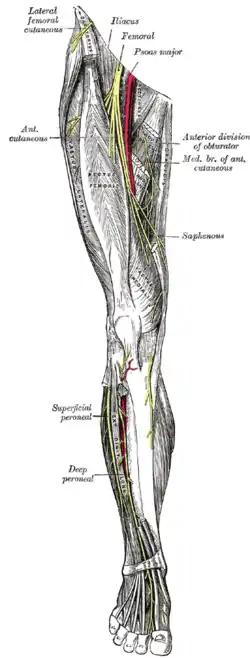

Nerve supply

The sensory and motor innervation to the lower limb is supplied by the lumbosacral plexus, which is formed by the ventral rami of the lumbar and sacral spinal nerves with additional contributions from the subcostal nerve (T12) and coccygeal nerve (Co1). Based on distribution and topography, the lumbosacral plexus is subdivided into the lumbar plexus (T12-L4) and the Sacral plexus (L5-S4); the latter is often further subdivided into the sciatic and pudendal plexuses:[45]

The lumbar plexus is formed lateral to the intervertebral foramina by the ventral rami of the first four lumbar spinal nerves (L1-L4), which all pass through psoas major. The larger branches of the plexus exit the muscle to pass sharply downward to reach the abdominal wall and the thigh (under the inguinal ligament); with the exception of the obturator nerve which pass through the lesser pelvis to reach the medial part of the thigh through the obturator foramen. The nerves of the lumbar plexus pass in front of the hip joint and mainly support the anterior part of the thigh.[45]

The genitofemoral nerve (L1, L2) leaves psoas major below the two former nerves, immediately divides into two branches that descends along the muscle's anterior side. The sensory femoral branch supplies the skin below the inguinal ligament, while the mixed genital branch supplies the skin and muscles around the sex organ. The lateral femoral cutaneous nerve (L2, L3) leaves psoas major laterally below the previous nerve, runs obliquely and laterally downward above the iliacus, exits the pelvic area near the iliac spine, and supplies the skin of the anterior thigh.[46]

The obturator nerve (L2-L4) passes medially behind psoas major to exit the pelvis through the obturator canal, after which it gives off branches to obturator externus and divides into two branches passing behind and in front of adductor brevis to supply motor innervation to all the other adductor muscles. The anterior branch also supplies sensory nerves to the skin on a small area on the distal medial aspect of the thigh.[47] The femoral nerve (L2-L4) is the largest and longest of the nerves of the lumbar plexus. It supplies motor innervation to iliopsoas, pectineus, sartorius, and quadriceps; and sensory branches to the anterior thigh, medial lower leg, and posterior foot.[47]

The nerves of the sacral plexus pass behind the hip joint to innervate the posterior part of the thigh, most of the lower leg, and the foot.[45] The superior (L4-S1) and inferior gluteal nerves (L5-S2) innervate the gluteus muscles and the tensor fasciae latae. The posterior femoral cutaneous nerve (S1-S3) contributes sensory branches to the skin on the posterior thigh.[48] The sciatic nerve (L4-S3), the largest and longest nerve in the human body, leaves the pelvis through the greater sciatic foramen. In the posterior thigh it first gives off branches to the short head of the biceps femoris and then divides into the tibial (L4-S3) and common fibular nerves (L4-S2). The fibular nerve continues down on the medial side of biceps femoris, winds around the fibular neck and enters the front of the lower leg. There it divides into a deep and a superficial terminal branch. The superficial branch supplies the fibularis muscles and the deep branch enters the extensor compartment; both branches reaches into the dorsal foot. In the thigh, the tibial nerve gives off branches to semitendinosus, semimembranosus, adductor magnus, and the long head of the biceps femoris. The nerve then runs straight down the back of the leg, through the popliteal fossa to supply the ankle flexors on the back of the lower leg and then continues down to supply all the muscles in the sole of the foot.[49] The pudendal (S2-S4) and coccygeal nerves (S5-Co2) supply the muscles of the pelvic floor and the surrounding skin.[50]